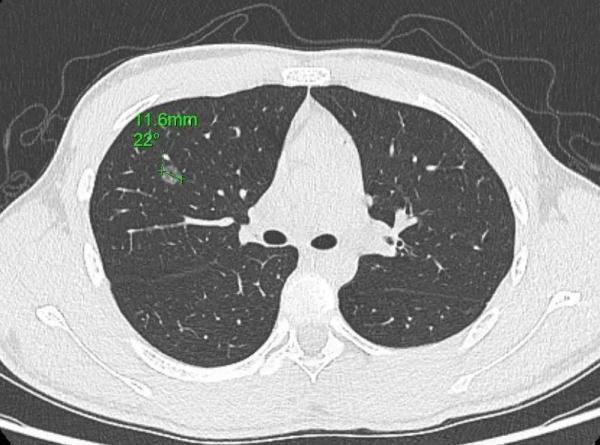

2021年底,14岁中学生小亮(化名)吃错药被送往医院抢救,当天CT检查时,医生意外发现他的右上肺有个磨玻璃结节。就在这几年,小亮家里好几位亲戚接二连三查出了肺结节,其中就包括小亮的姨妈、外婆、爷爷。

小亮的肺结节位于右上肺前段(1.16cm)

今年1月,父亲带着小亮和小亮外婆前往医院进一步就诊。通过复查胸部CT,医生发现两人的肺结节都有不同程度增大,需尽早手术。小亮和外婆当天就办了入院,并安排在同一天手术,好在两人手术都很成功。